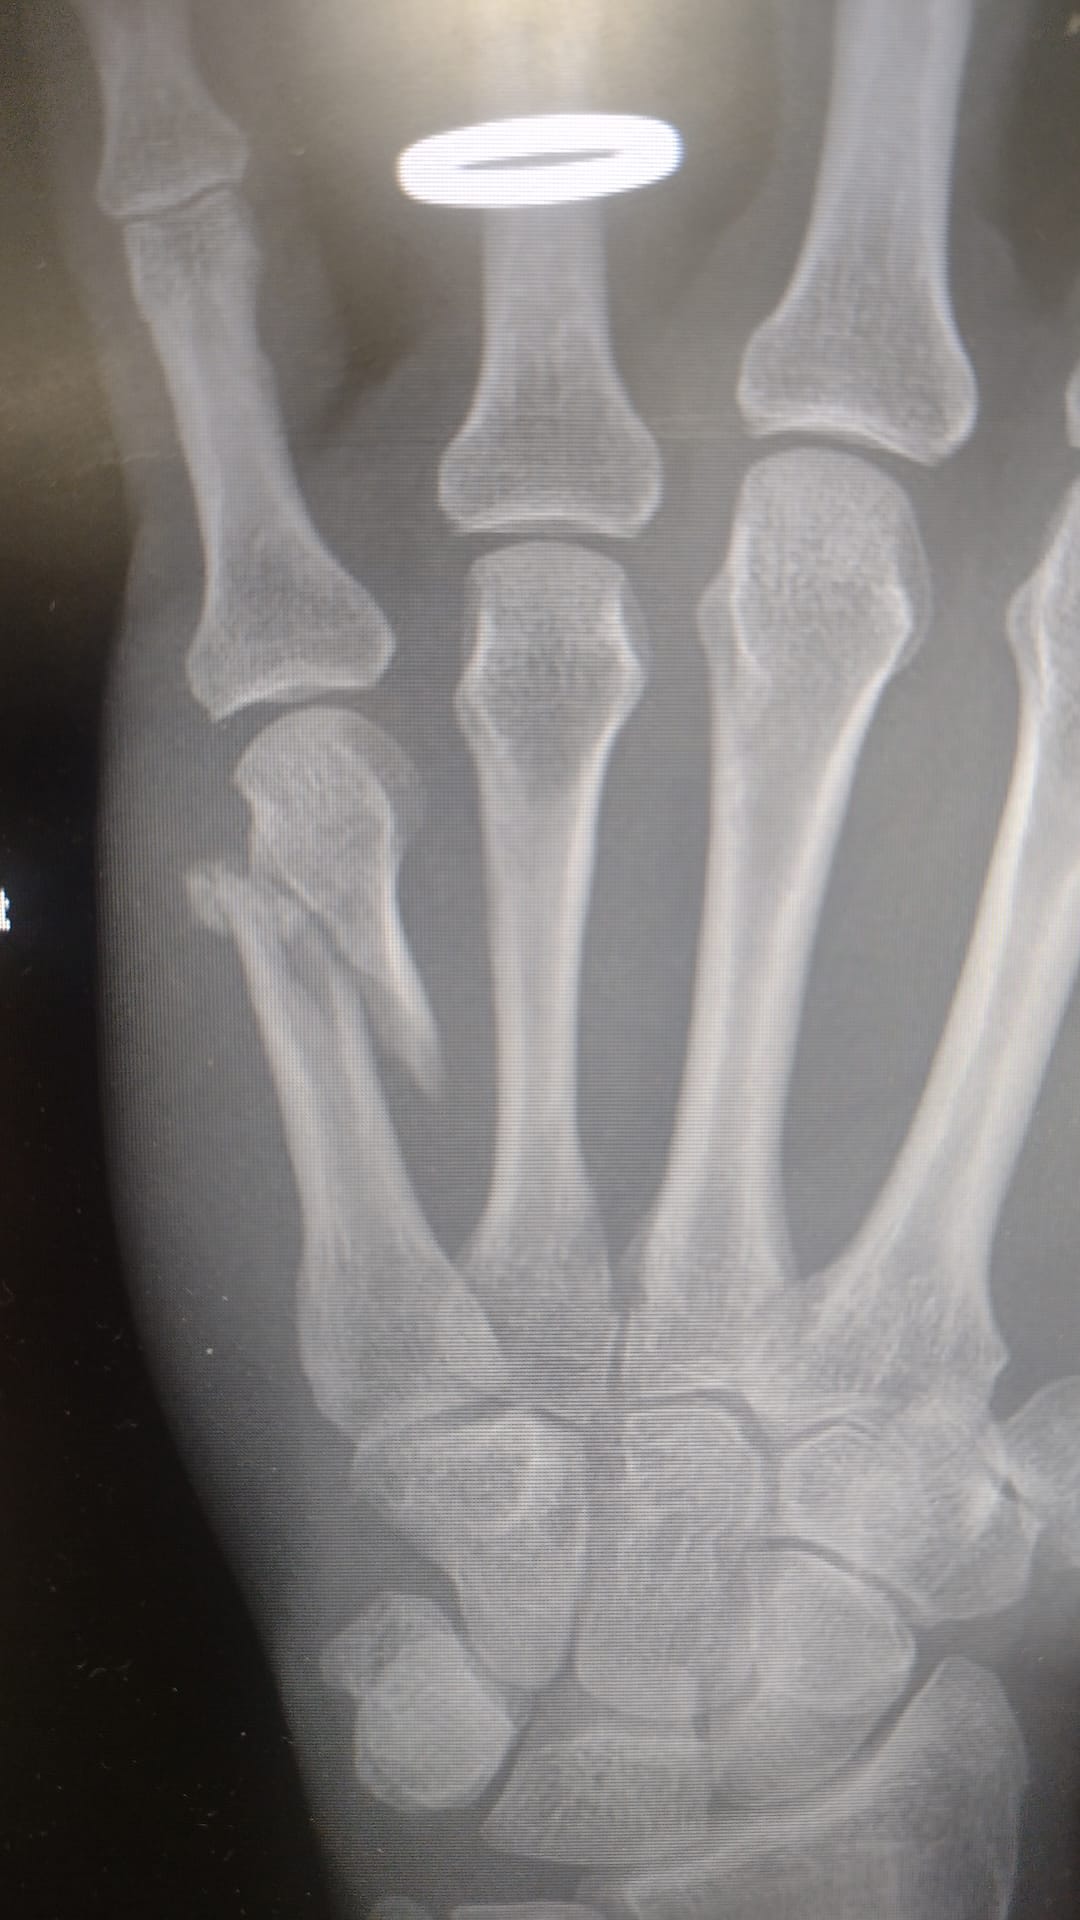

Last September, three days before the end of my Spanish holiday adventure, I decided to take a pootle into Salamanca along one of the many ‘greenways’ they have around Spanish cities. Near the end there was a little section of boardwalk off the side of a viewing platform of the Roman bridge so off I went. Literally… The front wheel slipped on the greasy surface and I landed on my left hand on the edge of the boardwalk. It hurt but I could still move my fingers so I set off back to the campsite. No sympathy from my partner but as my hand began to swell she did suggest I went to the hospital. However, we had a ferry to catch the following day so I thought it best to focus on getting back as the pain was bearable. Driving and taking bikes off and on of the bike rack was a bit uncomfortable though. Finally back in Sheffield, I trotted off to the minor injuries unit for an X-ray. The radiologist said “You’ve done a proper job on that!” and packed me off to the hand clinic. Two surgeries later and what looks on an X-ray like a piece of bike chain in the hand, the road (no mountain biking for a good while) to recovery started. Still a bit of discomfort eight months later but at least I am riding bikes off-road! Lesson: avoid family/commuter greenways.